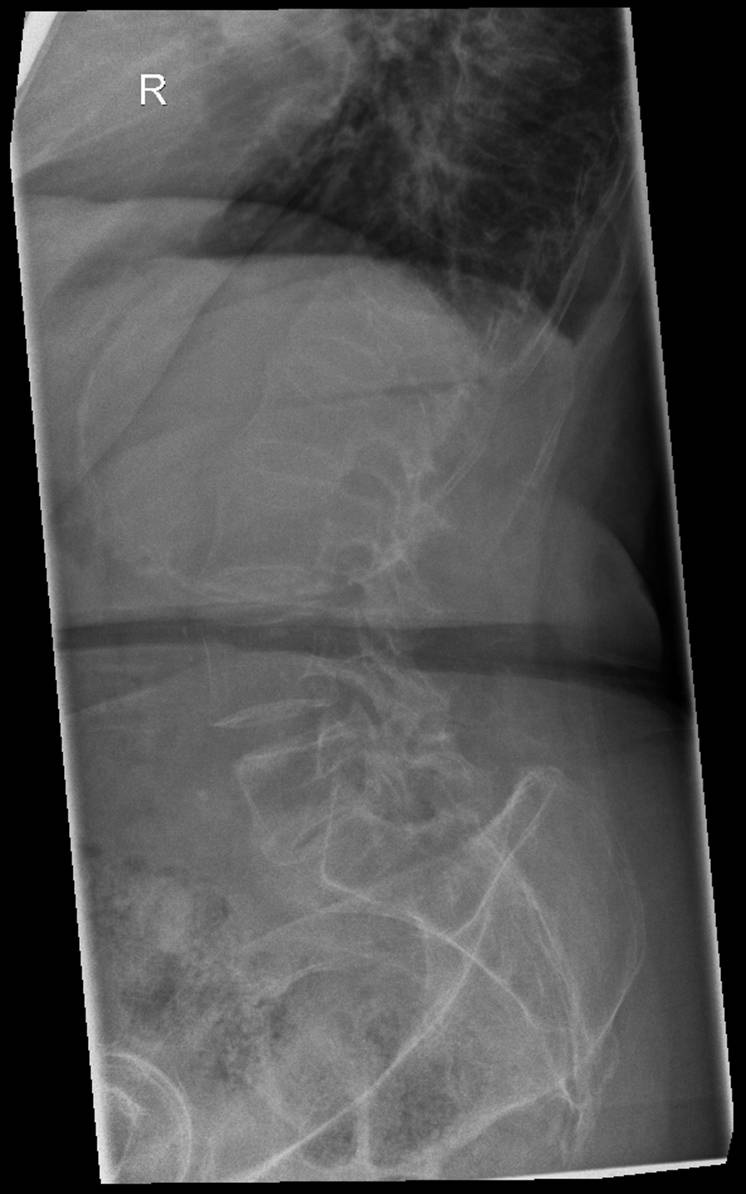

> Пациентка, 1934 г.р., постует 8 апреля к травматологам... упала дома на

> спину... сильные боли в области перехода грудного в поясничный отдел

> позвоночника... Рентген... (первые две картинки)

> Выполняют КТ-позвоночника... (Третья и четвертая картинки)